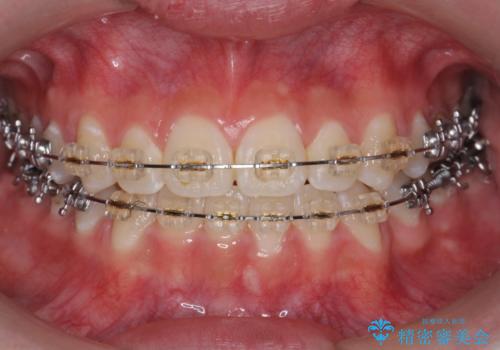

受け口 親知らずを取り込む矯正治療

- 矯正装置

- 審美装置

- 治療期間

- 3年2ヶ月

- 高校生で来院。受け口が主訴でした。

下の小臼歯を抜歯しましたが、その代わり下の親知らずを残して咬ませたので、歯の数は変わっていません。

ただし、左下の親知らずを残すには厚みのある歯ぐきを処置しています。(ディスタルウェッジ)

左上奥歯は、矯正後セラミックインレー修復を行なっています。